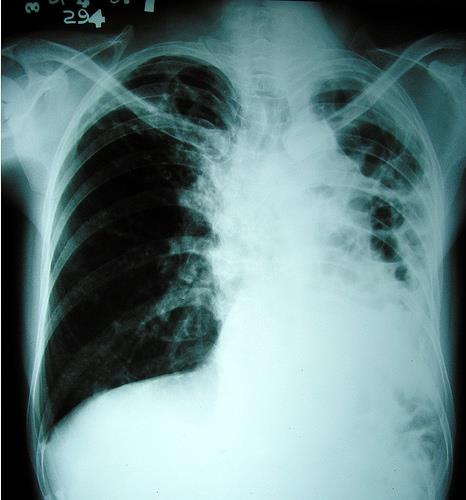

tuberculosis.